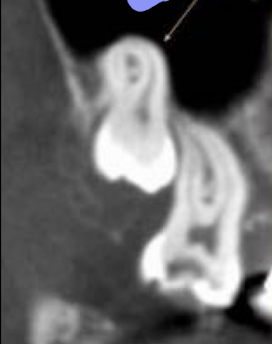

Dilaceration is a disturbance in tooth formation that produces a — — or — in the tooth anywhere in the crown or the root.

sharp bend or curve

Dilaceration is a disturbance in — — that produces a sharp bend or curve in the tooth anywhere in the — or the —.

tooth formation, crown, root

A disturbance in the root formation that produces a sharp bend or curve in the tooth anywhere in the crown or the root

dilaceration